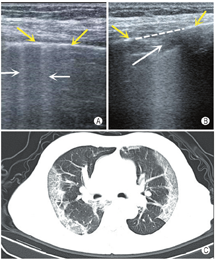

横向扫查时,显示光滑胸膜线,至少显示2条水平方向的A线;纵向扫查时表现为"蝙蝠征"(两侧肋骨声影与之间胸膜线构成)。正常肺部图像应显示胸膜线、A线,能够观察到肺滑动征(图4)。

胸膜线:胸膜与肺表面界面声阻抗差异形成的回声反射,呈光滑、清晰、规则的线性高回声。

A线:胸膜与肺界面声阻抗的差异产生多重反射而形成的伪像,位于胸膜线下方,呈一系列与之平行的光滑、清晰、规则的线性高回声,彼此间距相等,回声由浅入深逐渐减弱至消失。

肺滑动征:实时超声下可见脏层胸膜与壁层胸膜随呼吸运动而产生一种水平方向的相对滑动。

沙滩征:M型模式扫查,可见由胸膜线上方波浪线样的线性高回声与胸膜线下方由肺滑动产生的均匀颗粒样点状回声共同形成类似沙滩样表现的超声影像(图5)。